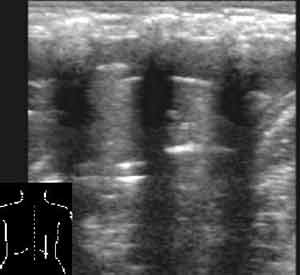

Эхография в диагностике заболеваний легких у детей.

Рис. 9. Поджатый безвоздушный край лёгкого, окруженный жидкостью.